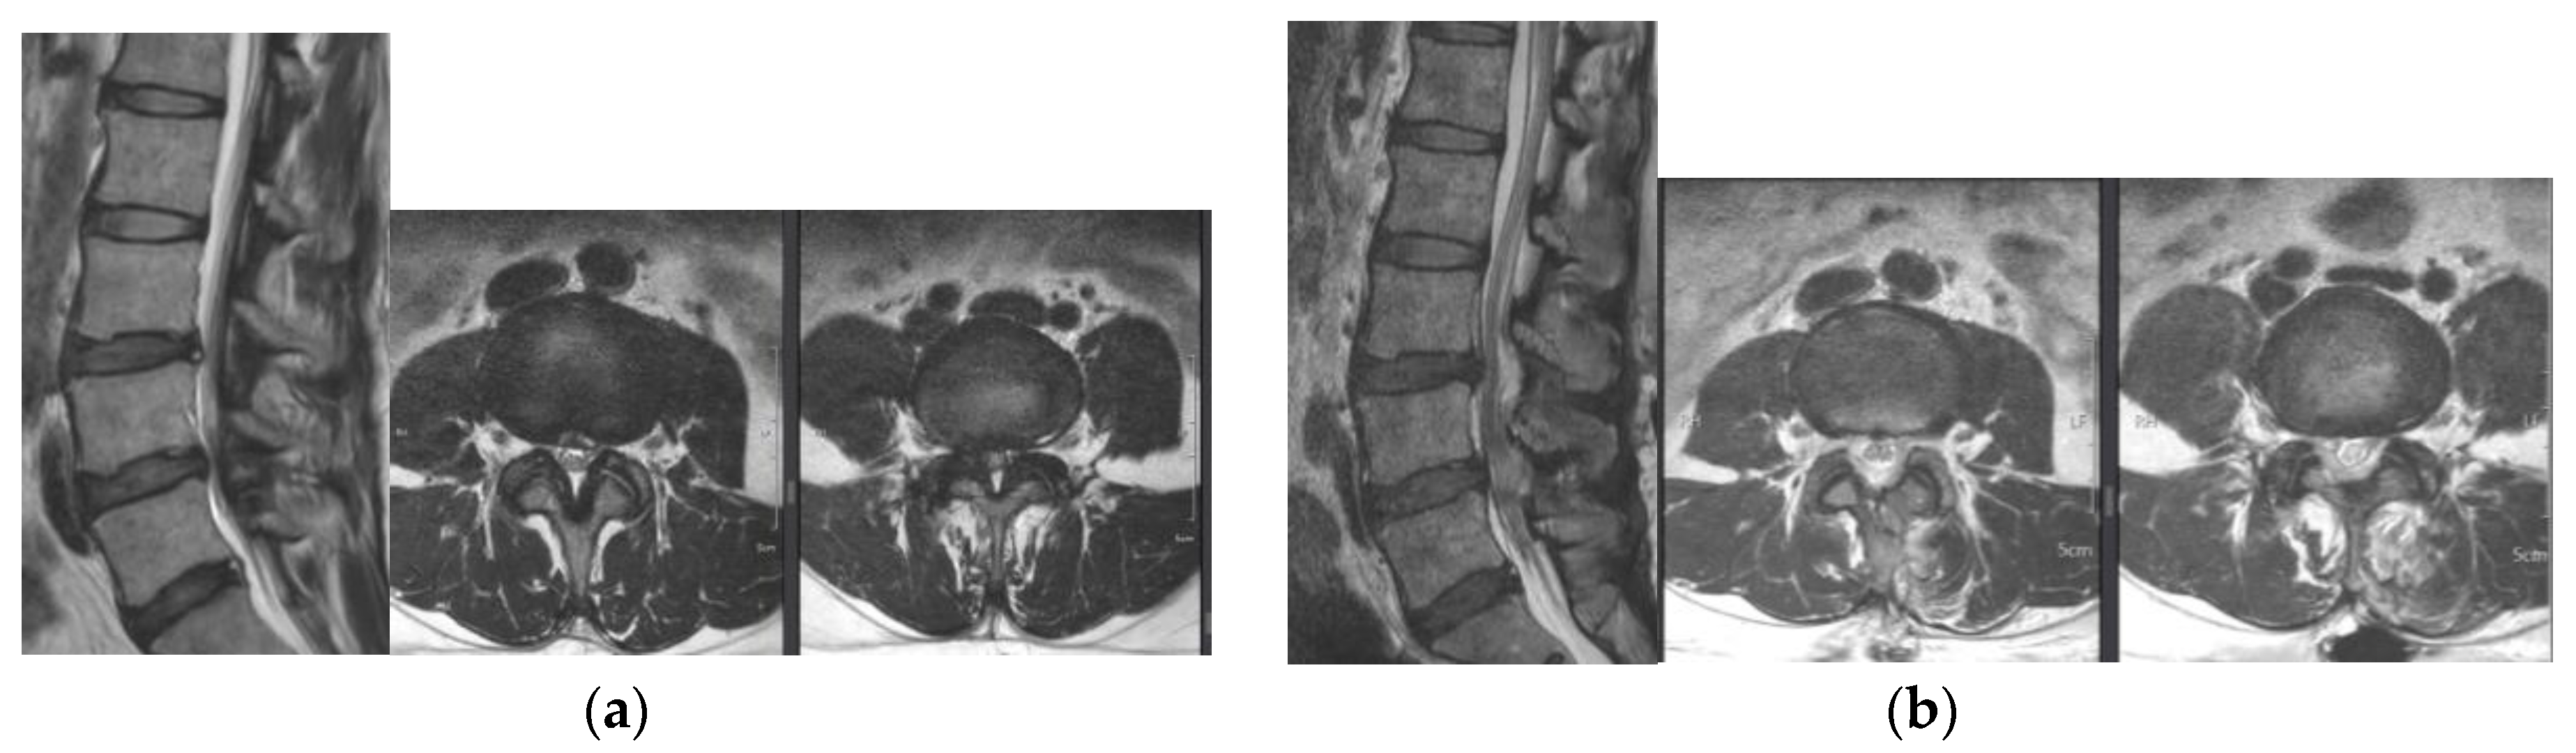

3.3. Radiologic Outcome Evaluation